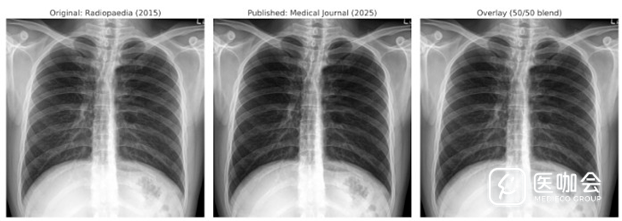

该学术侦探指出,2015年恶搞图片与2025年论文中的图像存在"完全一致的解剖特征",包括空气模式和骨骼结构,这些特征"即便在同一患者的不同扫描影像中也会存在差异"。

图. 愚人节发的图片和期刊发表图片的对比